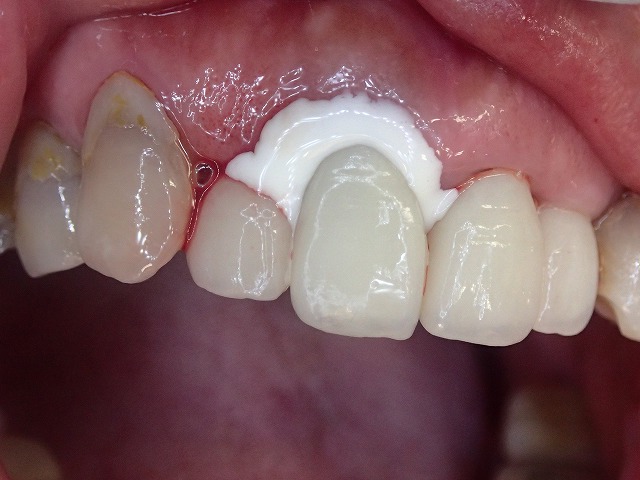

外れたジルコボンドクランをセメント合着

当方の美観からするとちょっとねえ。。。

患者さんから20年以上前に

制作したものだとお聞きしました。

製作時は歯の先端はきちんと

左右対処であったのだと思います。

神経のない歯 すなわち失活歯は、

歯根の先端に感染病巣がある場合が多く

わずかな病巣でも、自己免疫反応で

歯が浮き上がってくる場合があります。

この事例も同じだと考えられます。

このままでは気分がよくないので、綺麗にしてあげよう。

第一段階 まだまだ・・・・